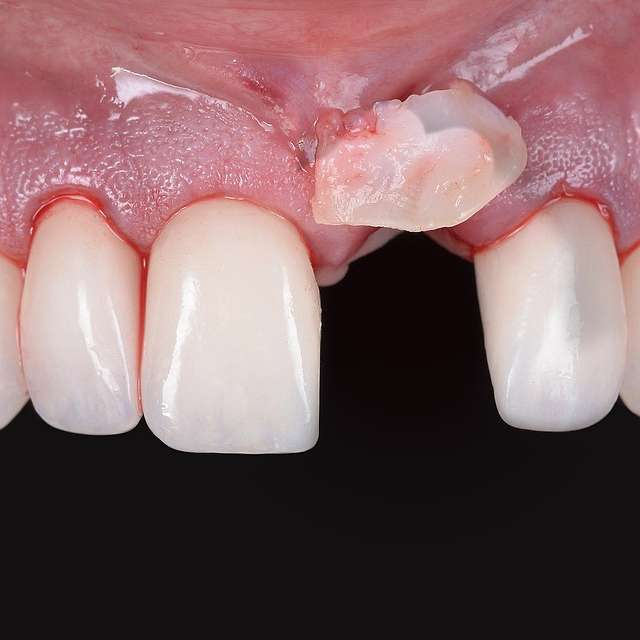

Grefa gingivala este o micro-chirurgie prin care se transplanteaza o mica bucata de tesut moale - gingie sau tesut conjuctiv (stratul intern al gingiei) pentru a acoperi un defect gingival. De obicei, acest tip de interventie este necesar pentru augmentarea implanturilor dentare, sau pentru a acoperi defecte cauzate de traume sau de afectiuni parodontale.Grefele se recolteaza din zona molarului de minte, sau de pe palat, si sunt transplantate in zona afectata.

Acesta interventie este una foarte delicata, lamele folosite pentru a efectua procedura sunt aceleasi folosite in oftalmologie, iar firele de sutura sunt si ele foarte fine. Firele se indeparteaza dupa 7-14 zile, in functie de caz, cand are loc vindecarea primara. Maturarea grefei dureaza aproximativ 90 zile, de aceea in momentul inserarii implanturilor preferam sa facem si grefa de tesut, pentru a sincroniza timpii de vindecare si ambelor proceduri.

Grefe pentru corectia defectelor gingivale